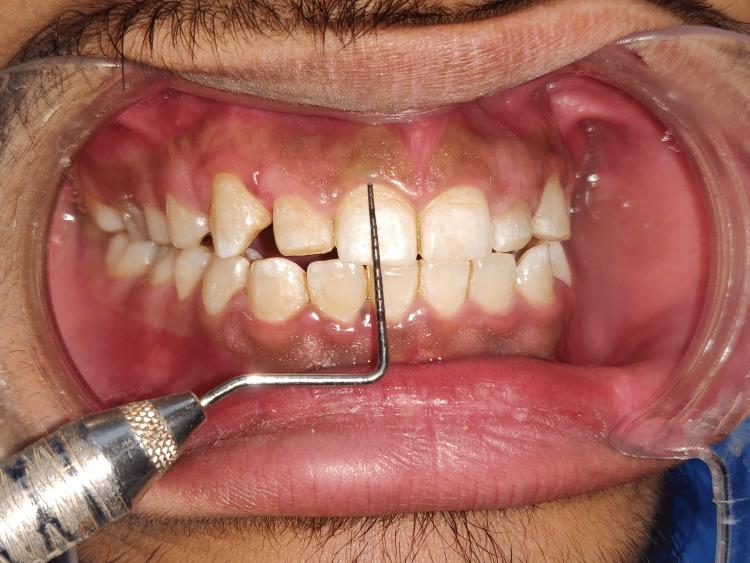

因被动萌出异常导致的露龈笑的牙周治疗:一例报告

Periodontal Management of Gummy Smile Due to Altered Passive Eruption: A Case Report.

Today's population is expanding quickly, and there is a growing desire for aesthetics. Smiles and other friendly facial expressions communicate joy and assurance. They are the essential elements of nonverbal communication and play a significant part in establishing a person's first impression. The altered passive eruption, which results in the excessive gingival display (EGD) when the gingival edge is situated incisal to the cervical convexity of the crown, is one of the factors affecting aesthetics. It has an impact on the patient's appearance and grin. The management of EGD becomes crucial. The following case study covers the control of EGD with a crown lengthening operation.

摘要

当今人口迅速增长,人们对美学的追求也与日俱增。微笑及其他友好的面部表情传达着喜悦和自信。它们是非语言交流的关键要素,在形成一个人的第一印象中起着重要作用。当牙龈边缘位于牙冠颈部凸度的切端时,会导致牙龈过度显露(EGD)的被动萌出改变,这是影响美学的因素之一。它会影响患者的外貌和笑容。因此,对EGD的处理变得至关重要。以下病例研究涵盖了通过牙冠延长术控制EGD的情况。